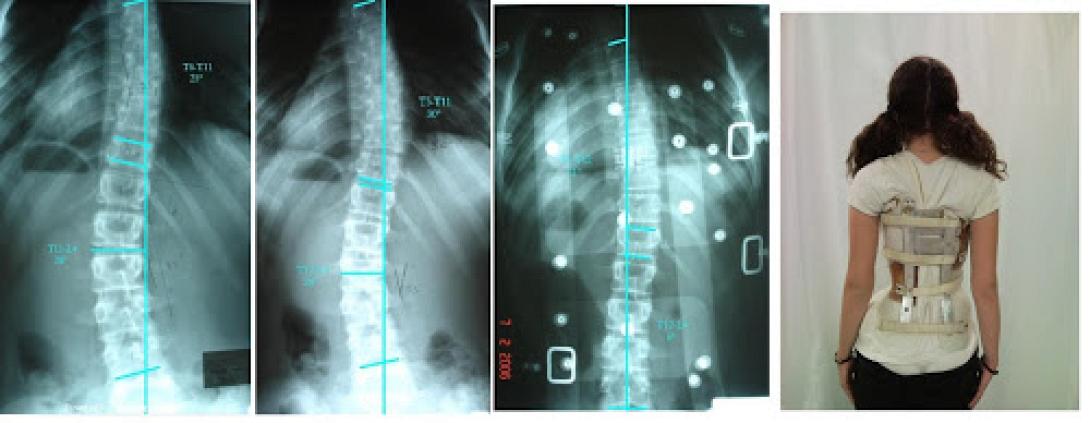

Την Παρασκευή 28 Νοεμβρίου 2014 από 6:30 – 8:30 μ.μ. θα πραγματοποιηθεί επιστημονική εκδήλωση στο Αμφιθέατρο του Πα.Γ.Ν.Η., η οποία διοργανώνεται από την Πανεπιστημιακή Ορθοπαιδική Κλινική, (Δ/ντής ο Καθηγητής Γ.Μ. Κοντάκης).

Προσκεκλημένος ομιλητής είναι ο κύριος Θάνος Τσιρίκος, Διευθυντής της Κλινικής Σπονδυλικής Στήλης για παιδιά, του Πανεπιστημιακού Νοσοκομείου του Εδιμβούργου, και ο οποίος θα αναπτύξει το θέμα: «Παραμορφώσεις της Σπονδυλικής Στήλης – Σκολίωση: Συντηρητική και χειρουργική θεραπεία».

Το θέμα της διάλεξης θεωρείται ιδιαίτερα ενδιαφέρον αφού ο κ. Τσιρίκος είναι ένας από τους κορυφαίους Χειρουργούς στο Ηνωμένο Βασίλειο για την αντιμετώπιση των παθήσεων αυτών.